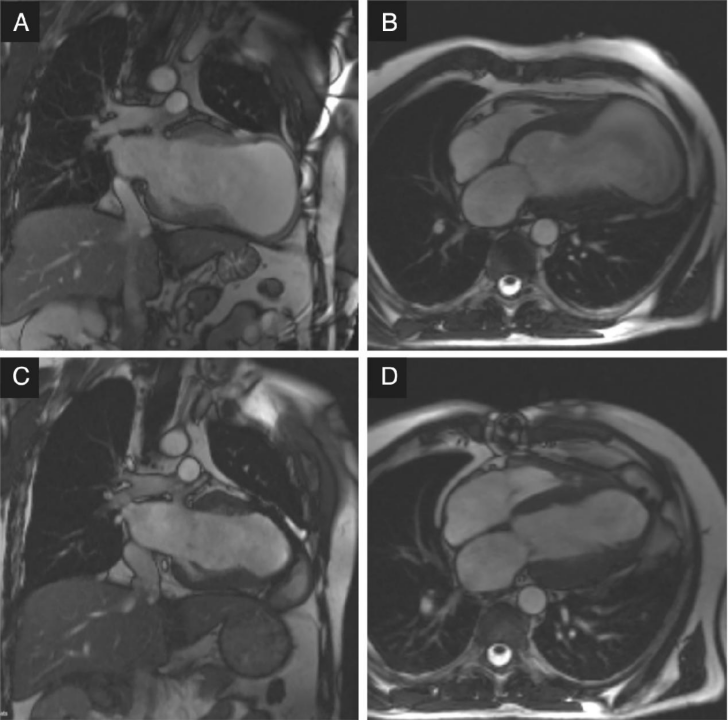

手术前后心脏的磁共振图像如下所示:手术前拍摄的现场图像显示心肌梗死后有一个大的心尖动脉瘤,伴有心室容积增加和室壁变薄[双腔方向(A);四腔定向(B)]。手术后 6 个月拍摄的图像显示左心室容积显著减少和重塑 [双腔方向 (C);四腔定向(D)]。

12个月时,左室射血分数显著改善(29%vs.34%,P<0.005)观察到左室容积减少(左室收缩末和舒张末容积指数均下降:分别为74mL/m2和54mL/m2,P<0.001;106mL/m2和80mL/m2,P<O.0001),术后一年患者生存率为90.6%。